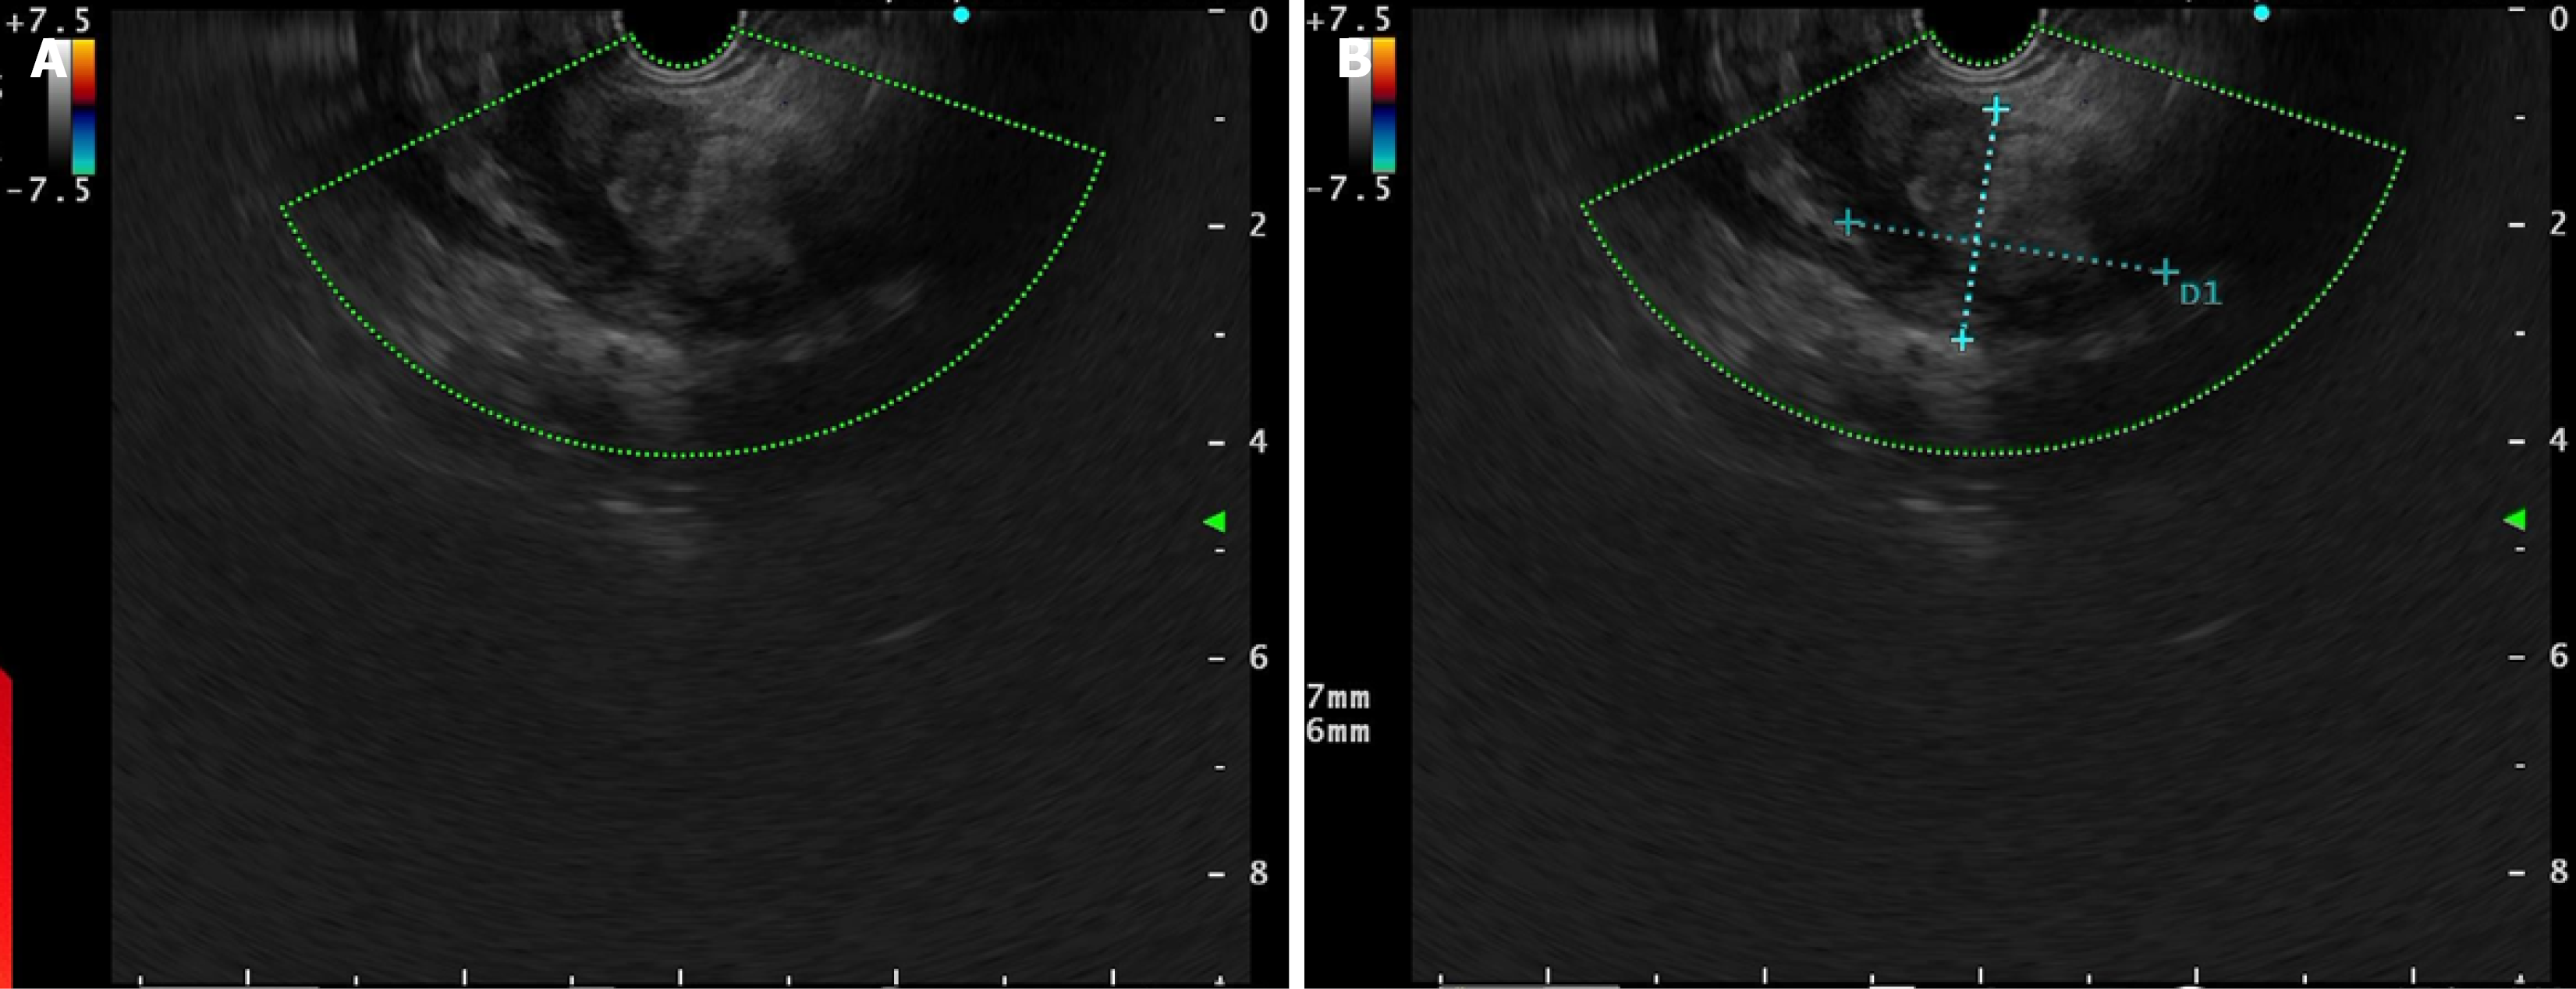

Contrast-enhanced abdominal CT demonstrated irregular thickening of the gastric antral wall with heterogeneous enhancement. A cystic lesion (3.4 cm × 2.2 cm) was found adjacent to the lesser curvature of the gastric antrum, exhibiting thick-walled morphology, blurred margins, and mild enhancement post-contrast (Figure 1). Two omental nodules near the inferior liver margin and enlarged lymph nodes in the hepatogastric ligament and mesentery were observed. MRI revealed an abnormal signal lesion (2.8 cm × 1.5 cm) lateral to the lesser curvature of the gastric antrum, showing hyperintensity on T1 weighted imaging (T1WI) (Figure 2), hypointensity on T2 weighted imaging (T2WI) (Figure 2), and no enhancement post-contrast (Figure 2). The vertical-axis ultrasound gastroscopy scan shows a uniform echo in the gastric body. A low-echo mass-like change approximately 3.0 cm × 2.2 cm in size is observed on the outer wall of the gastric antrum (Figure 3), with uneven internal echoes and visible high-echo structures (Figure 3). Based on the imaging findings, a hematoma or inflammatory lesion was suspected, with malignancy not excluded.

In our case, we showed the image of AA under ultrasound gastroscopy for the first time, where low-echo mass-like changes outside the gastric antrum wall, uneven internal echoes, and high-echo structures were seen. This is different from the imaging manifestations of AA with medium-high echoes and rich blood vessels[22,23] under conventional percutaneous B-ultrasound. This may also suggest that the ultrasound images of AA in rare sites and those in common sites may be different.